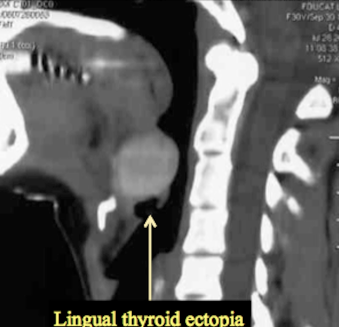

Thyroide linguale ectopique

- DD: Thyroide linguale ectopique (Toujours chercher si le patient à une thyroide, une thyroide ectopique est associée dans 40% des cas), Adénopathie, Kyste Dermoide, Kyste des arc branchiaux (plus latéral++),